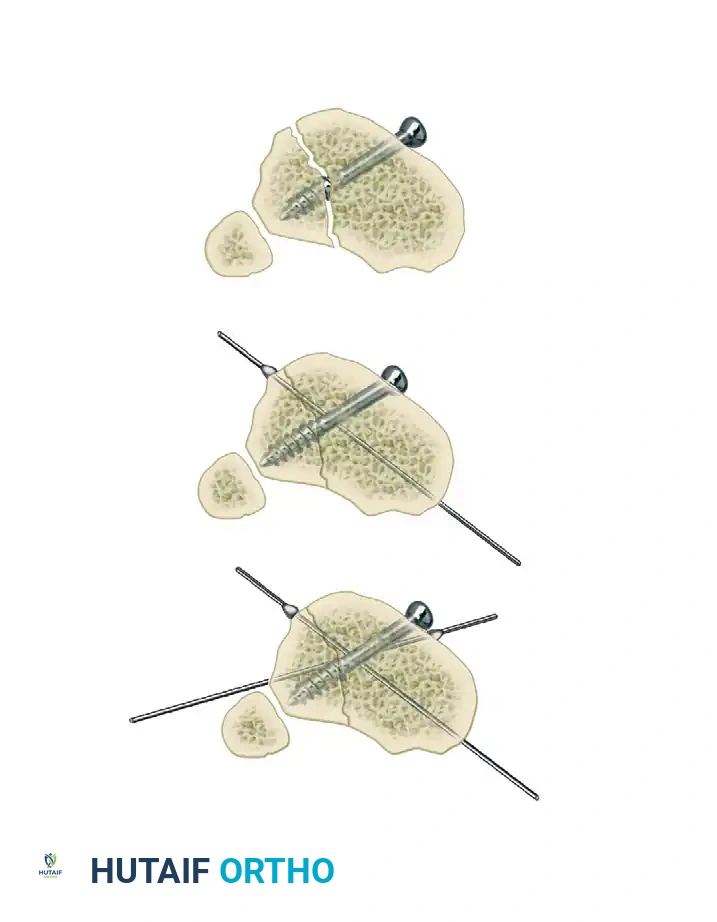

Step 3: Multi-Planar Fracture Reduction Using Olive Wires

Olive wires (wires with a small metal bead or "olive" forged into them) are powerful tools for translating bone fragments and achieving final reduction.

- Coronal Plane Correction: Use arched olive wires for final fracture reduction. For residual displacement in the coronal plane, place an olive wire in a transverse fashion (ensuring it passes through a safe anatomical zone).

- Apply tension to the wire without securing it tightly to the frame on the opposite side. The tensioner will pull the olive—and consequently the bone fragment—toward the tensioner, correcting the translation.

- Use continuous image intensification to ensure adequate reduction is achieved without over-translating the fragment.

- Once adequate correction is obtained in the coronal plane, secure the wire to the frame on the olive side.

- Sagittal Plane Correction: If further correction is required in the sagittal plane, connect another olive wire in an arched fashion. Tensioning this arched wire will impart a directional force vector to the bone, achieving final sagittal alignment.

In rare cases involving specific oblique or spiral fracture patterns, two olive wires can be inserted from opposite sides, perpendicular to the fracture plane. As these wires are tensioned, they effect reduction and apply interfragmentary compression.

Clinical Pearl: While opposing olive wires can provide excellent compression, this pattern of wire placement may not always be anatomically safe due to the location of neurovascular structures.

If opposing olive wires cannot be placed safely, these specific fracture patterns may be fixed with one or more lag screws, followed by the application of the external fixator to neutralize bending and torsional forces. However, as previously warned, this should be reserved for specific metaphyseal or highly stable configurations, avoiding diaphyseal interfragmentary fixation when possible.